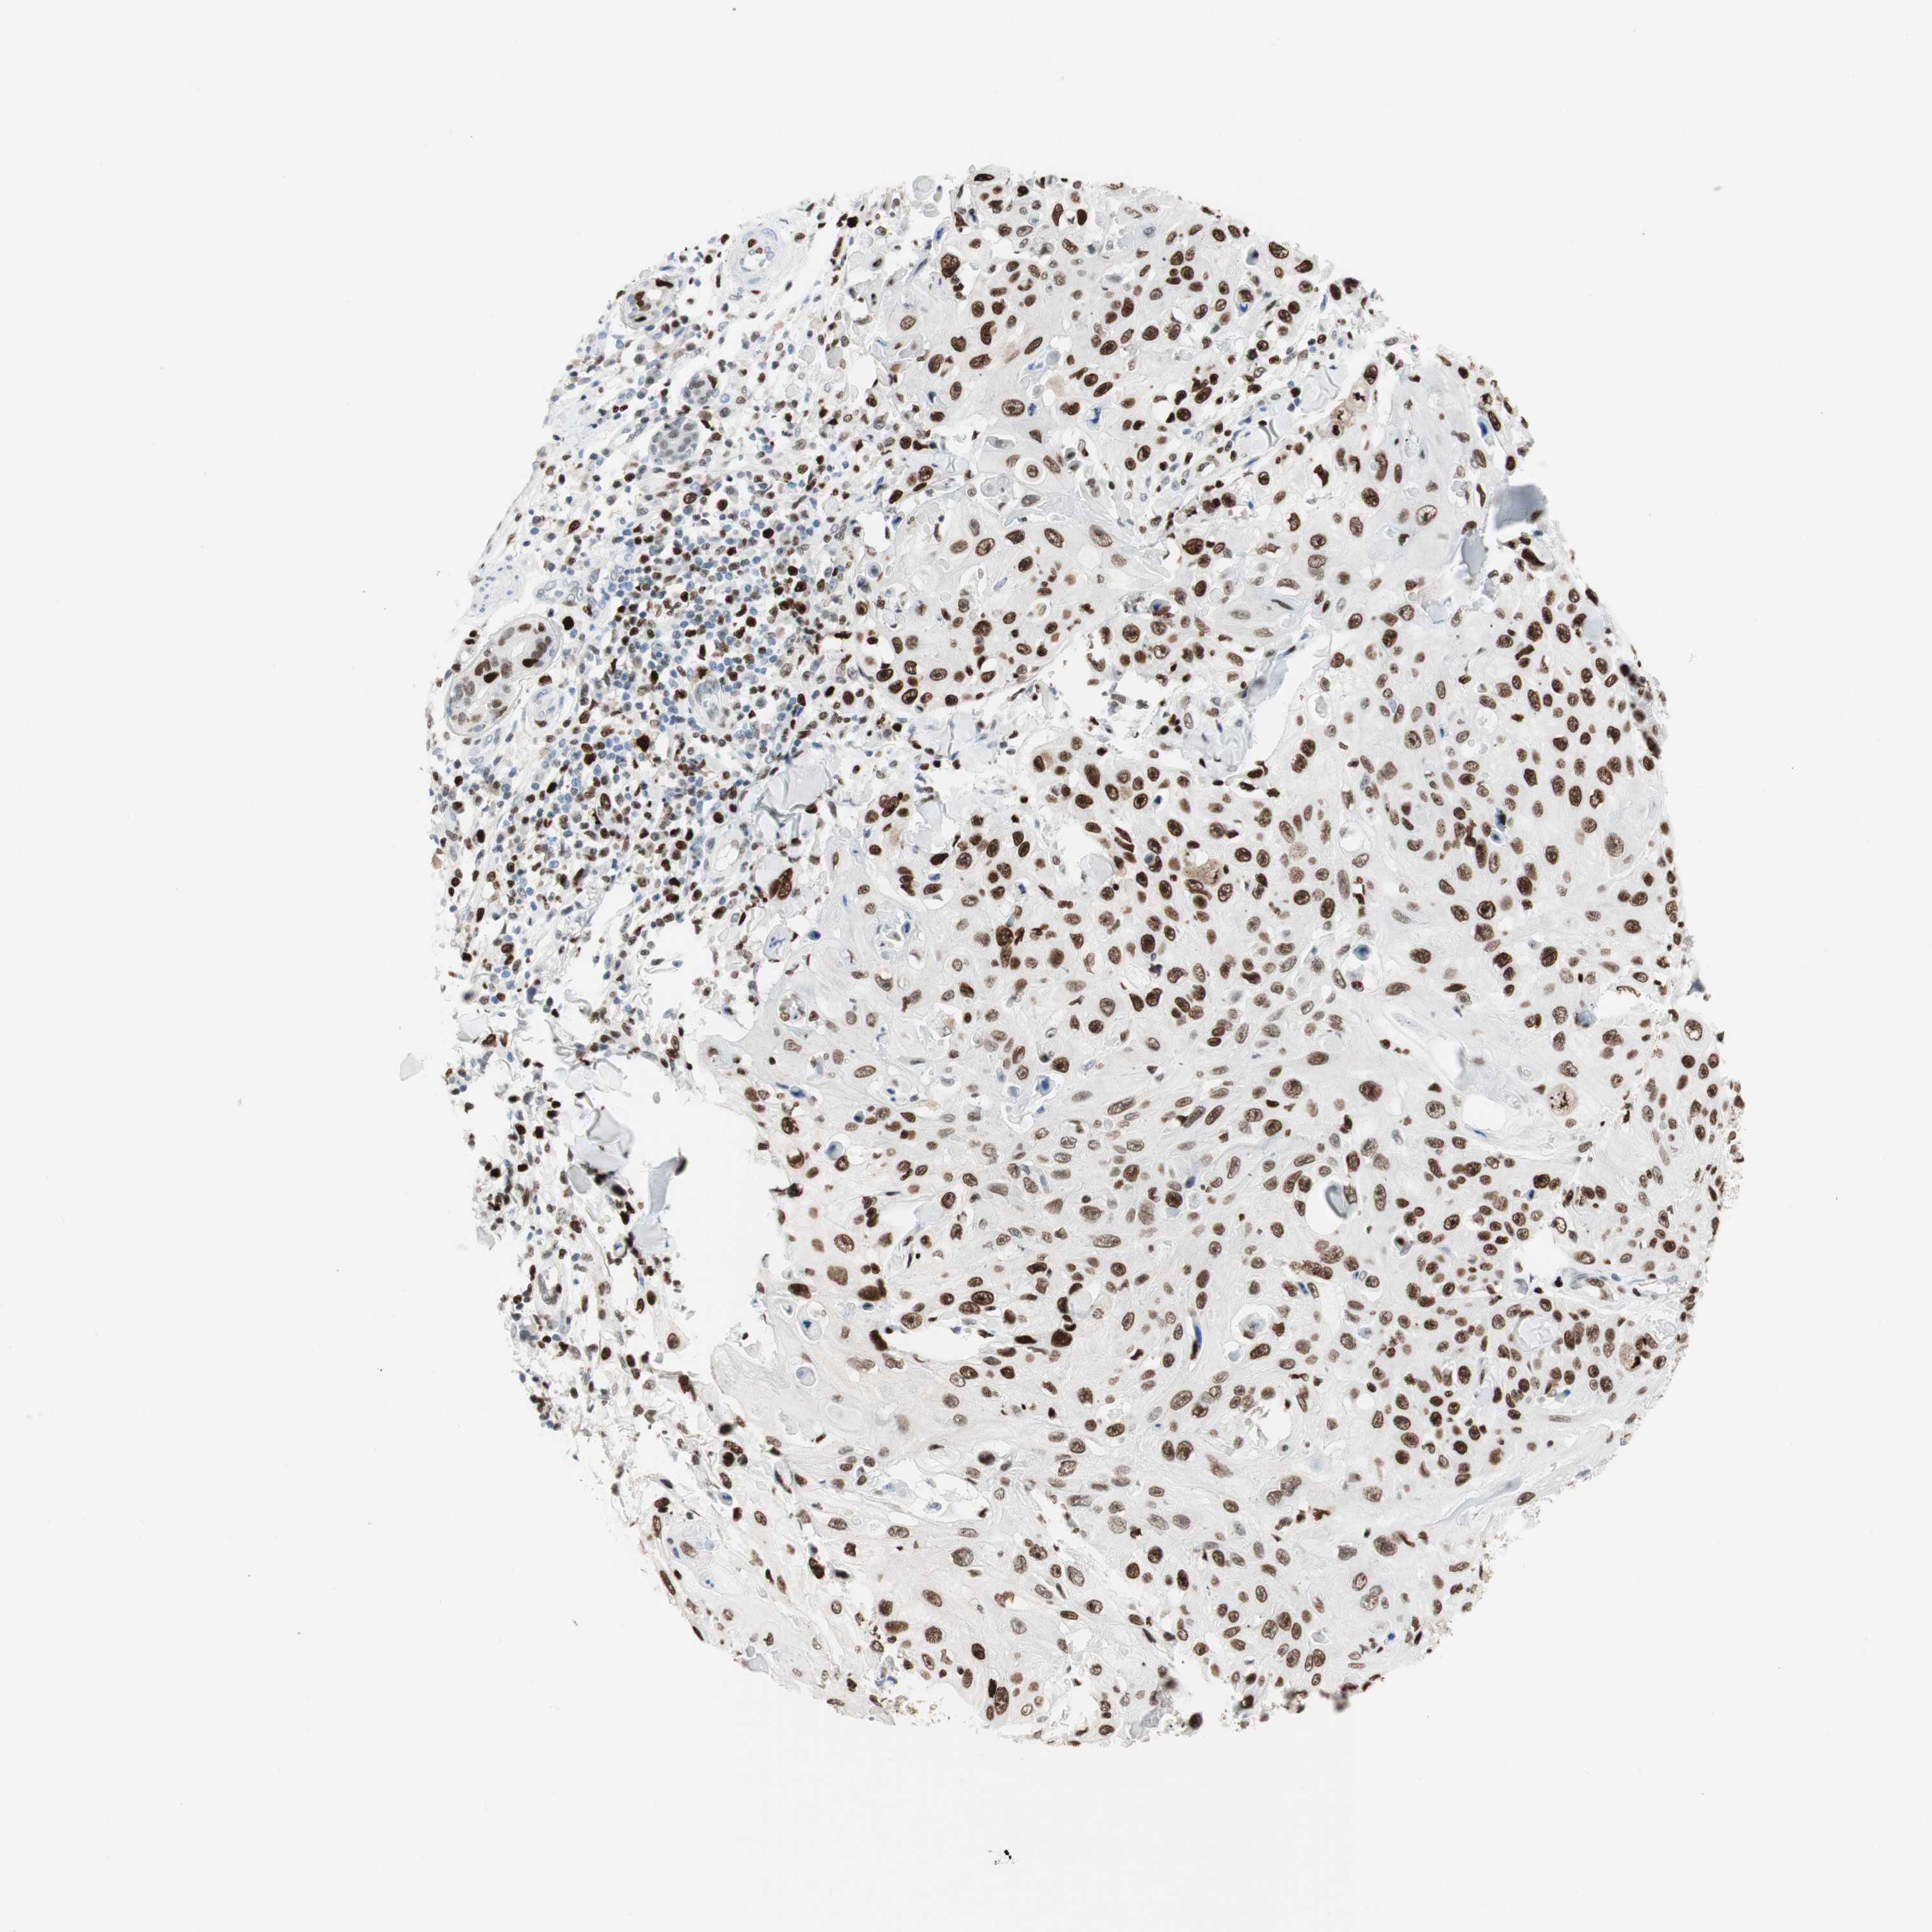

SKIN CANCER - Protein expressioni

A mouse-over function shows sample information and annotation data. Click on an image to view it in a full screen mode. Samples can be filtered based on level of antibody staining by selecting one or several of the following categories: high, medium, low and not detected. The assay and annotation is described here.

Antibody staining in the annotated cell types in the current human tissue is reported as not detected, low, medium, or high, based on conventional immunohistochemistry profiling in selected tissues. This score is based on the combination of the staining intensity and fraction of stained cells.

Each image is clickable and will lead to virtual microscopy that enables deeper exploration of all samples and also displays staining intensity scores, fraction scores and subcellular localization as well as patient and tissue information for each sample.

Antibody CAB009589

Squamous cell carcinoma, NOS